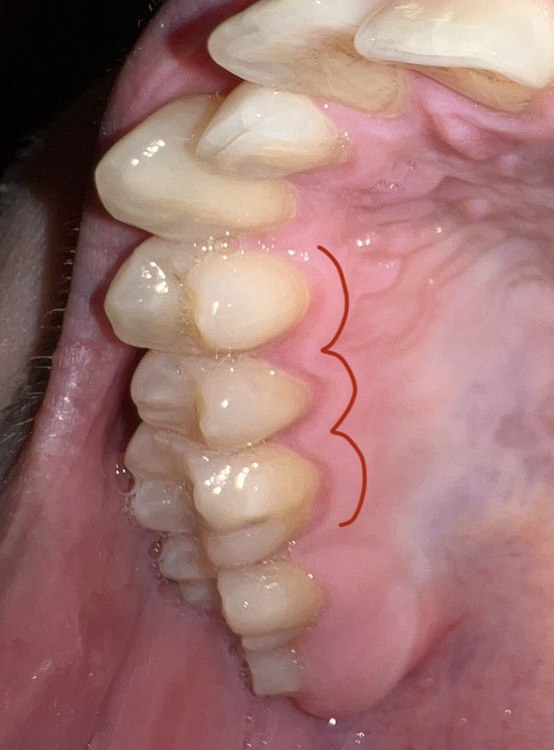

Десны, на месте где зубы в них входят такая вот хуйня, отметил рядом если не понятно. Это начало парадонтита или чего-то такого? Камень года 3 не ходил чистить, каюсь. Есть связь с камнем?